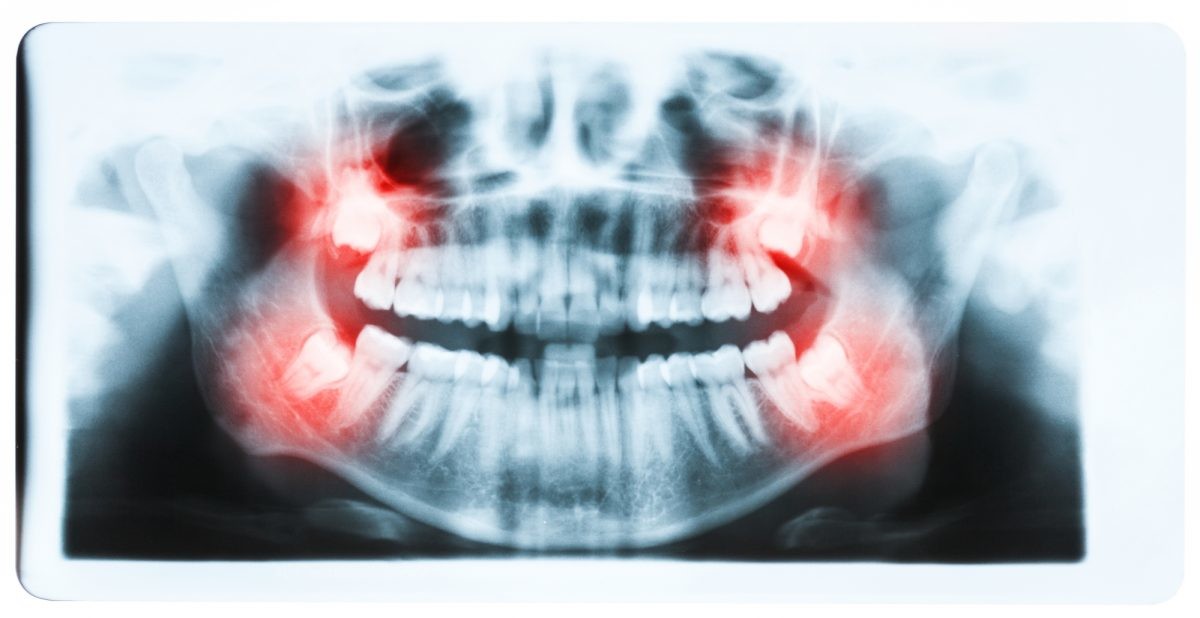

If a wisdom tooth becomes impacted or doesn’t erupt straight up, this can cause significant problems for the person. While some people may experience absolutely no problems with their wisdom teeth or get lucky enough to not have any of these extra molars at all, others may experience problems with them.

Fortunately, impacted tooth removal is a common procedure and can provide relief from any pain and discomfort caused by these teeth. In fact, wisdom teeth removal is more common than dental implant procedures, which about three million people have every year.